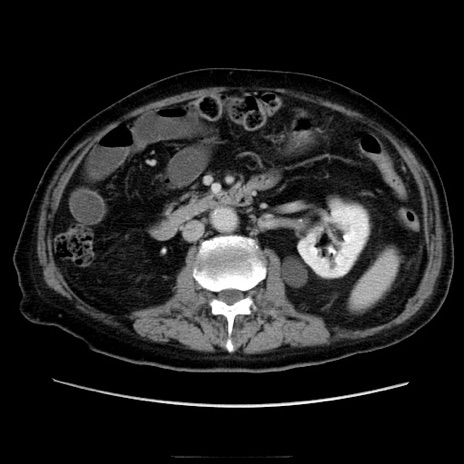

症例21(横断像)

【症例】70歳代男性

【主訴】腹痛

【現病歴】肝硬変・肝細胞癌にてかかりつけの方。約9時間前に食後より腹痛出現。症状が徐々に増悪し、嘔吐出現したため来院。

【既往歴】肝硬変、肝細胞癌(RFA、TACE後)

【身体所見】意識清明、表情苦悶様、BT 36℃、BP 129/78mmHg、P 88bpm、SpO2 97%(RA)、右上腹部から心窩部にかけて圧痛あり、反跳痛なし、筋性防御あり。

【データ】WBC 5800、CRP 0.16